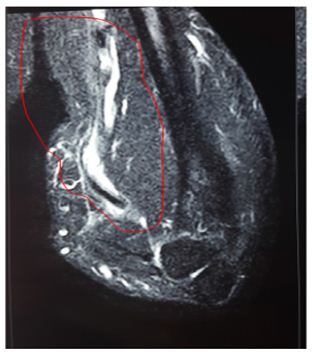

On ‘hook test’ (Figure 2) we could not hook finger around any anterior structures with elbow in flexed and supinated position. Pre operative quick DASH score was 57. X-ray showed no bony abnormality and an MRI confirmed complete rupture (Figure 3) and marked retraction of distal biceps tendon from bicipital tuberosity of the radius. Since the duration of injury was just one month we planned for reinsertion of tendon to bicipital tuberosity using fibre wire and an anchor screw. After pre anaesthesia evaluation patient was taken up for surgery. We went through anterior approach using a curved single incision over antecubital fossa without a tourniquet, and retrieved the tendon from the superior part of the incision (Figure 4).

Figure 3: MRI showing complete rupture and marked retraction of distal beceps tendon from bicipital tuberosity of radius.